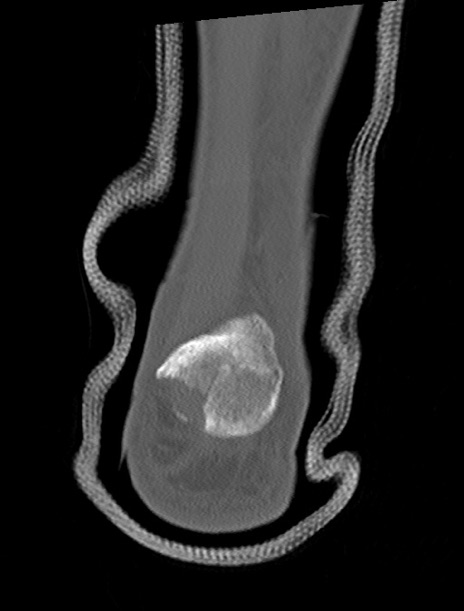

症例37 左足関節CT(冠状断像)

左足関節CT

矢状断像